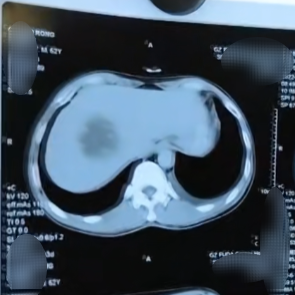

随着医疗技术的不断发展,“移动消融”这一技术已不仅仅只用在甲状腺病变中。如这位八十多岁的胰腺癌患者,其胰腺肿瘤将近六公分,还包绕着血管,已经无法手术了。对于这样的患者,我在化疗的基础上联合纳米刀消融术。术中纳米刀针尖将六公分的肿瘤分成一段段,利用“移动消融”慢慢消融整个肿瘤,整个消融过程非常顺利,达到了灭活肿瘤,同时也减少对身体的伤害。

还有这一位患者是转移性肝癌。肿瘤靠近膈肌临近血管,冷热消融风险比较大,所以最终选择了对正常组织伤害比较小的纳米刀消融。可肿瘤不规则发展,且有七公分左右,只能分区域进行“移动消融”,才能尽可能把边边角角的病灶消掉。